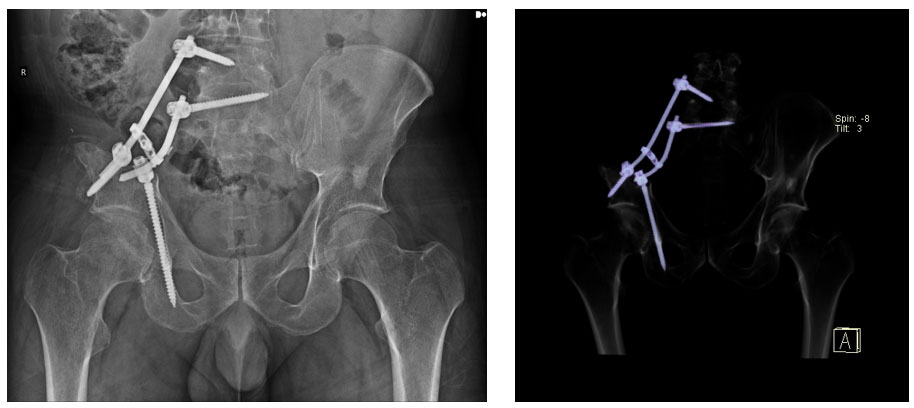

Ameliyat sonrası: Sakroiliak rezeksiyon sonrası rod ve vidalar ile yapılan fiksasyon görülmekte